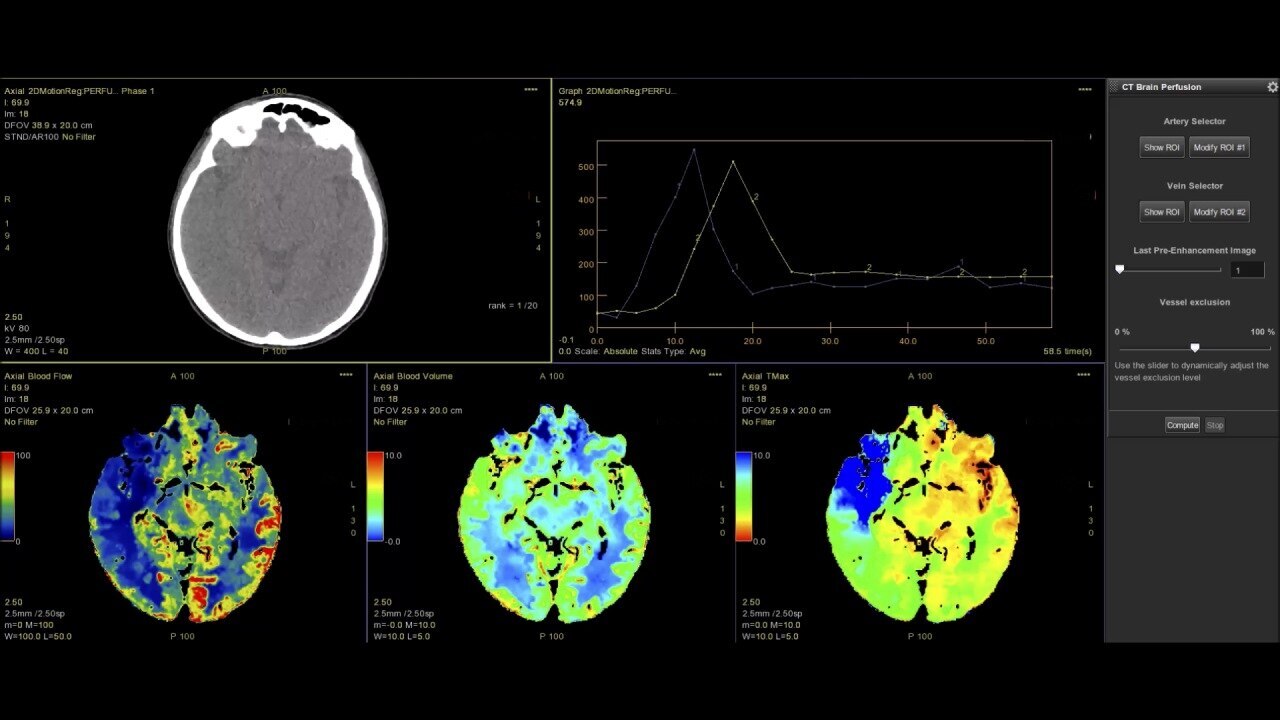

Perfusion maps and tissue classification

• Fully integrated with CT Perfusion 4D for visualization of perfusion functional maps³

• Deep Learning brain ventricle segmentation to prevent ventricular matter inclusion in quantitative results and improve visual inspection of the maps

• Automated computation of the functional maps

• Tissue Classification map segmented from absolute or relative values, customizable thresholds and user selectable input maps

• Mismatch volume and ratio calculated from the Modified Perfusion region and the Low Perfusion region